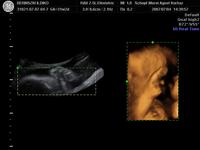

Szóval tegnap voltunk dokinál, méhszáj zárt, minden rendben, Máté pedig szép ütemben fejlődik. Óriásbaba nem lesz, de nem is baj, végülis valahogy elő is kell bújnia egy olyan kisebb kiszerelésű testből, mint az enyém. Ellenben rendezkedik odabent rendesen, meg feszít ezerrel. Élvezem nagyon, kivéve, mikor boxolja a hólyagomat. Meg van egy pont, amit mindig nyom, na az már kezd elég érzékennyé válni.

Aminek örülök: már több, mint 2 hete fejvégű. Remélem, így is marad. (Mellesleg lehet, hogy mégis forgolódik valahogy, mert elég amorf néha a pocim). Keményedések is vannak egyre sűrűbben, de általában csak 1-2 percig tartanak.